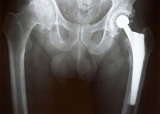

Οι ερευνητές του πανεπιστημίου του Μπρίστολ, με επικεφαλής την ‘Αλισον Σμιθ, που έκαναν τη σχετική δημοσίευση στο ιατρικό περιοδικό «The Lancet», σύμφωνα με το BBC και το πρακτορείο Ρόιτερ, μελέτησαν σε βάθος το ζήτημα (πάνω από 402.000 εμφυτεύματα) και συμπέραναν ότι μέσα σε πέντε χρόνια από την εγκατάστασή τους το 6,2% των πλήρως μεταλλικών εμφυτευμάτων ισχίου δεν λειτουργούσαν πια σωστά, έναντι ποσοστού αποτυχίας μόνο 2,3% των κεραμικών εμφυτευμάτων και 1,7% όσων είναι μικτά (μεταλλικά και πλαστικά).

Ο κίνδυνος αποτυχίας, σύμφωνα με τα στοιχεία, είναι μεγαλύτερος για τις γυναίκες (έως τέσσερις φορές μεγαλύτερος σε σχέση με τους άνδρες, αν και οι τελευταίοι έχουν τριπλάσια πιθανότητα να χρειαστούν τέτοιο εμφύτευμα), καθώς και για τους νέους και γενικότερα για τα μεταλλικά εμφυτεύματα που είναι μεγάλου μεγέθους. Κάθε αύξηση του μεγέθους κατά ένα χιλιοστό εκτιμάται ότι αυξάνει τον κίνδυνο δυσλειτουργίας κατά 2%. Αντίθετα, τα κεραμικά εμφυτεύματα φαίνεται πως λειτουργούν καλύτερα, όσο αυξάνει το μέγεθός τους.

Όμως, σύμφωνα με την αρμόδια βρετανική Ρυθμιστική Αρχή στον τομέα της υγείας (MHRA), όσοι έχουν τοποθετήσει στο σώμα τους μεταλλικά εμφυτεύματα, χρειάζεται να κάνουν τεστ αίματος κάθε χρόνο, επειδή μπορεί μικροσκοπικά κομματάκια τοξικού μετάλλου να αποσπώνται από το εμφύτευμα και να εισέρχονται στο κυκλοφορικό σύστημα. Αυτό είναι πιθανό να προκαλέσει ζημιά στους μυς και στα οστά ή νευρολογικό πρόβλημα.